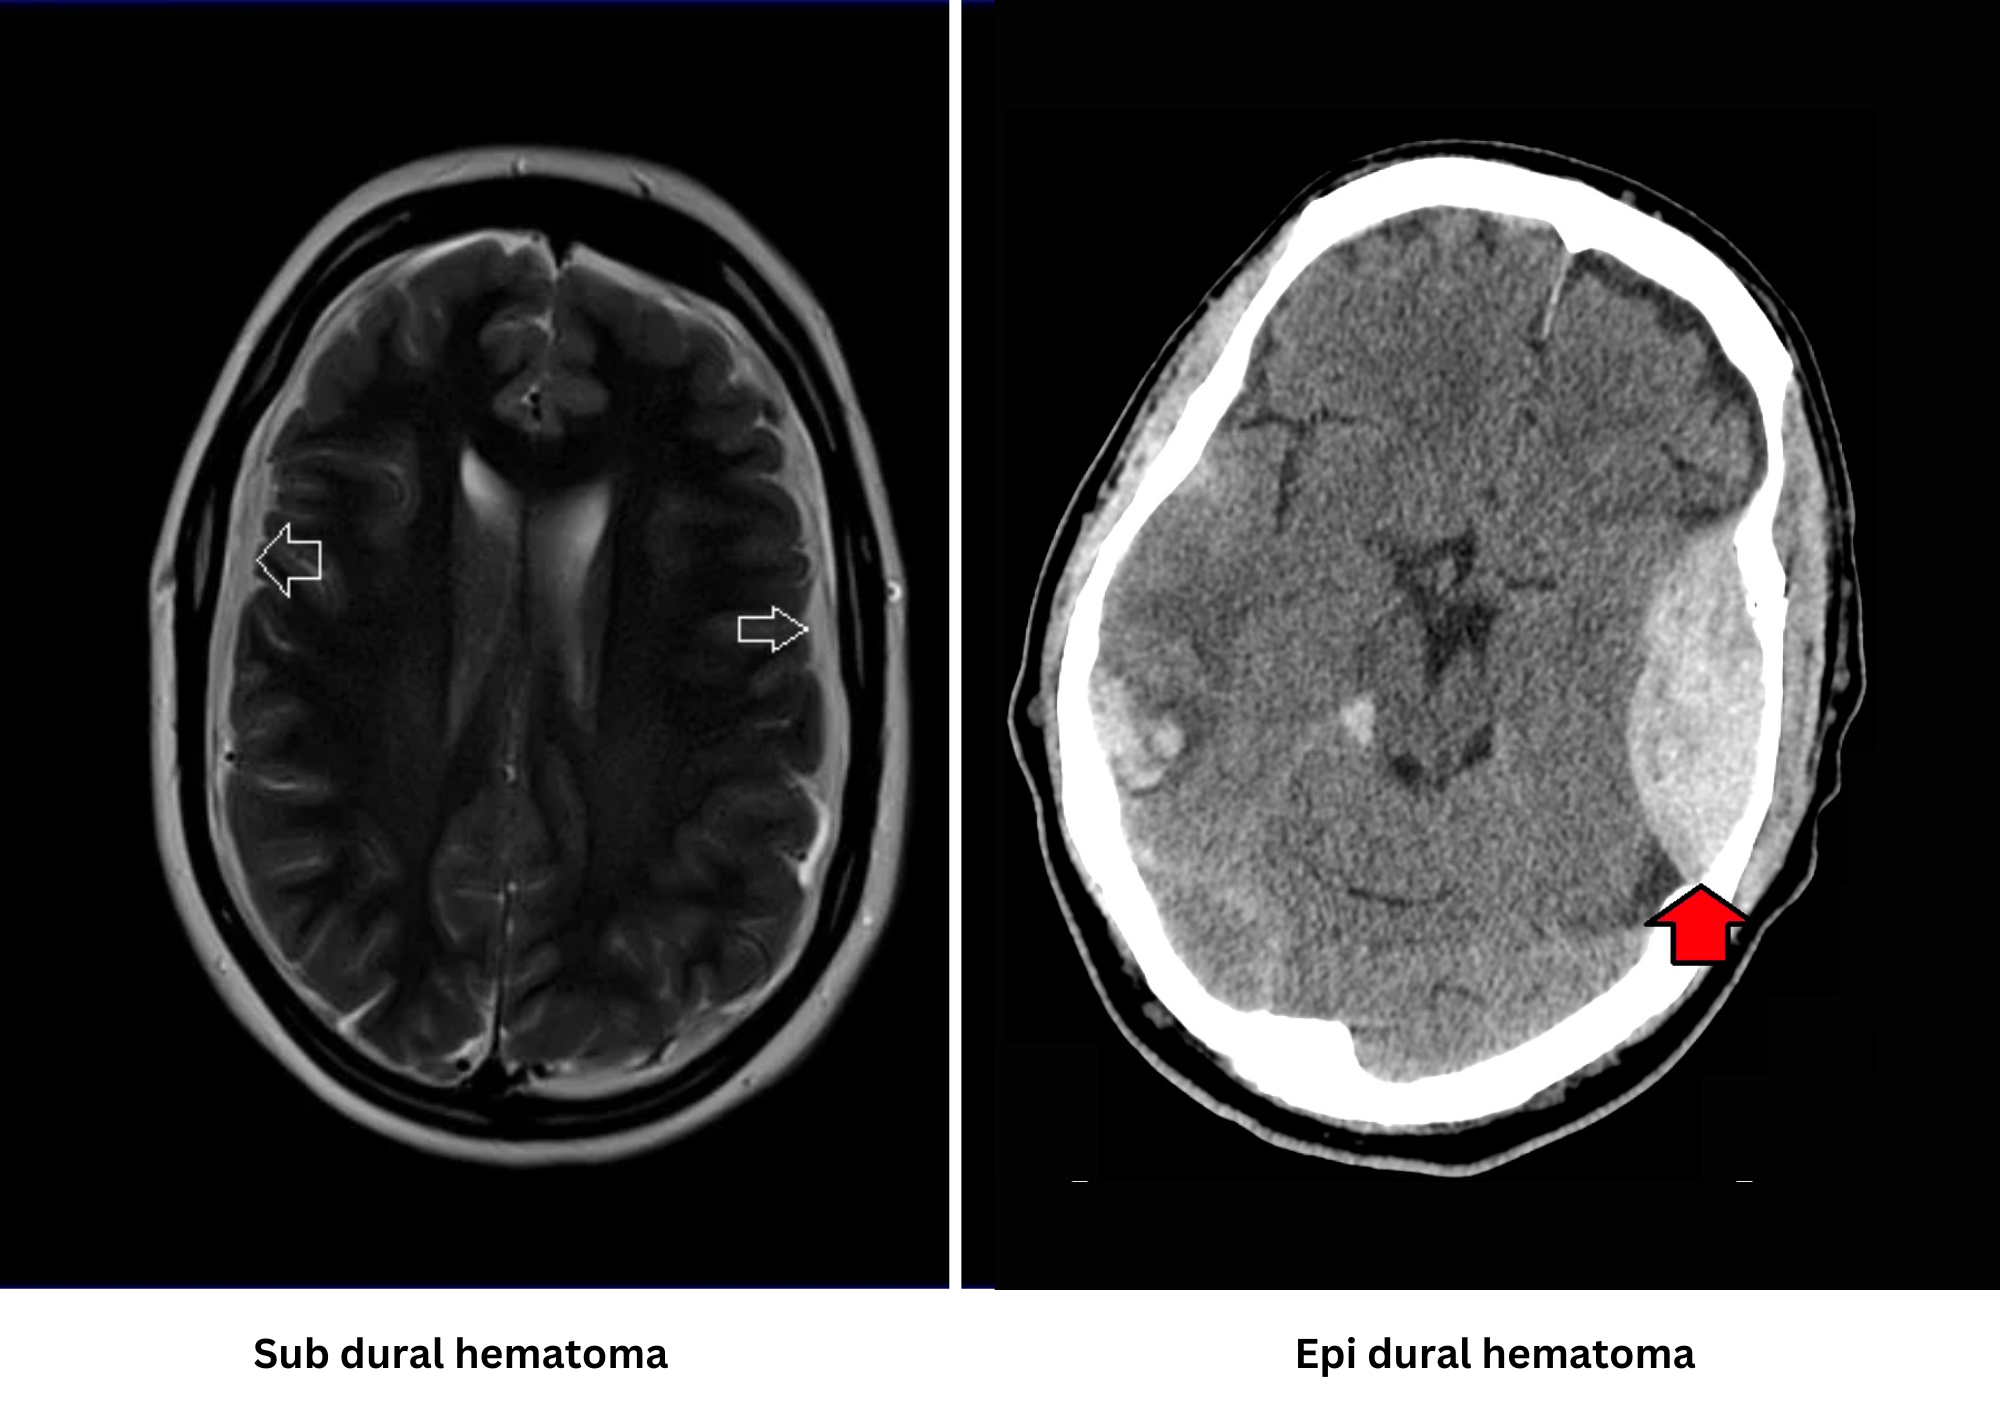

Many different kinds of brain injuries can cause headaches, back discomfort, memory loss, epi or subdural hematomas, and even paralysis. There are two categories for the symptoms: moderate and severe. Severe traumatic brain injury can cause bleeding, ruptured brain tissues, and other physical damage to the brain, whereas mild trauma can just temporarily impact brain cells. Indications of minor traumatic brain injury include physical signs like headache, vomiting, fatigue, and speech difficulties. Sensory symptoms may manifest as changes in smell, ear ringing, taste alterations, or impaired eyesight. Mental and cognitive issues include unconsciousness, confusion, focus/memory problems, mood fluctuations, anxiety, depression, and sleep disturbances. Furthermore, there could be instances of concussions.

Figure 2. Subdural hematoma and Epidural hematoma (source: mrimaster.com and wikipedia.org, resp.)

Some of the signs that may be displayed in moderate to severe traumatic brain injury are not shown where there is mild injury. Symptoms include occasional convulsions, confusion, frequent or worsening headache, vomiting, continuous or frequent unconsciousness, dilated pupils, clear water from the ear or nose, tiredness, weak muscles, and poor coordination. Cognitive-related symptoms include severe disorientation, unpredictable temper, difficulty speaking, and disturbances in consciousness; which could culminate in a coma.